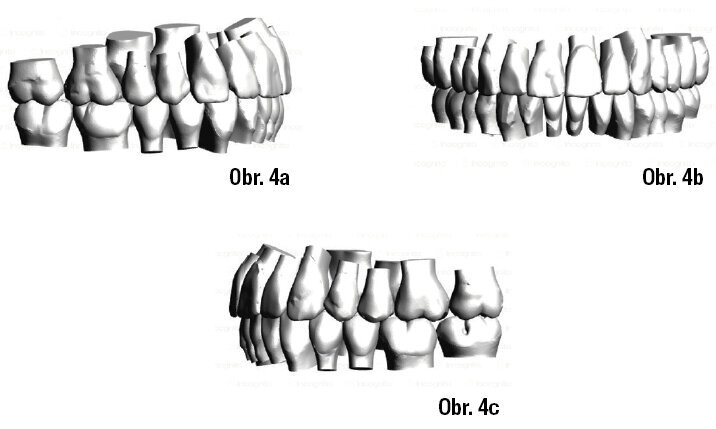

Analýza případu byla provedena pomocí programu 3M™ Unitek™ Treatment Management Portal/TMP – konečným výsledkem má být vyhovující okluze s I. třídou v molárech a špičácích a vyrovnanými středy zubních oblouků (obr. 4a–c).